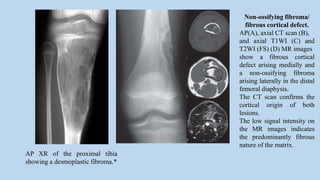

Non-ossifying fibroma/

fibrous cortical defect.

AP(A), axial CT scan (B),

and axial T1WI (C) and

T2WI (FS) (D) MR images

show a fibrous cortical

defect arising medially and

a non-ossifying fibroma

arising laterally in the distal

femoral diaphysis.

The CT scan confirms the

cortical origin of both

lesions.

The low signal intensity on

the MR images indicates

the predominantly fibrous

nature of the matrix.